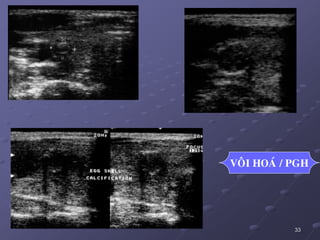

PGH

VOÂI HOAÙ / PGH